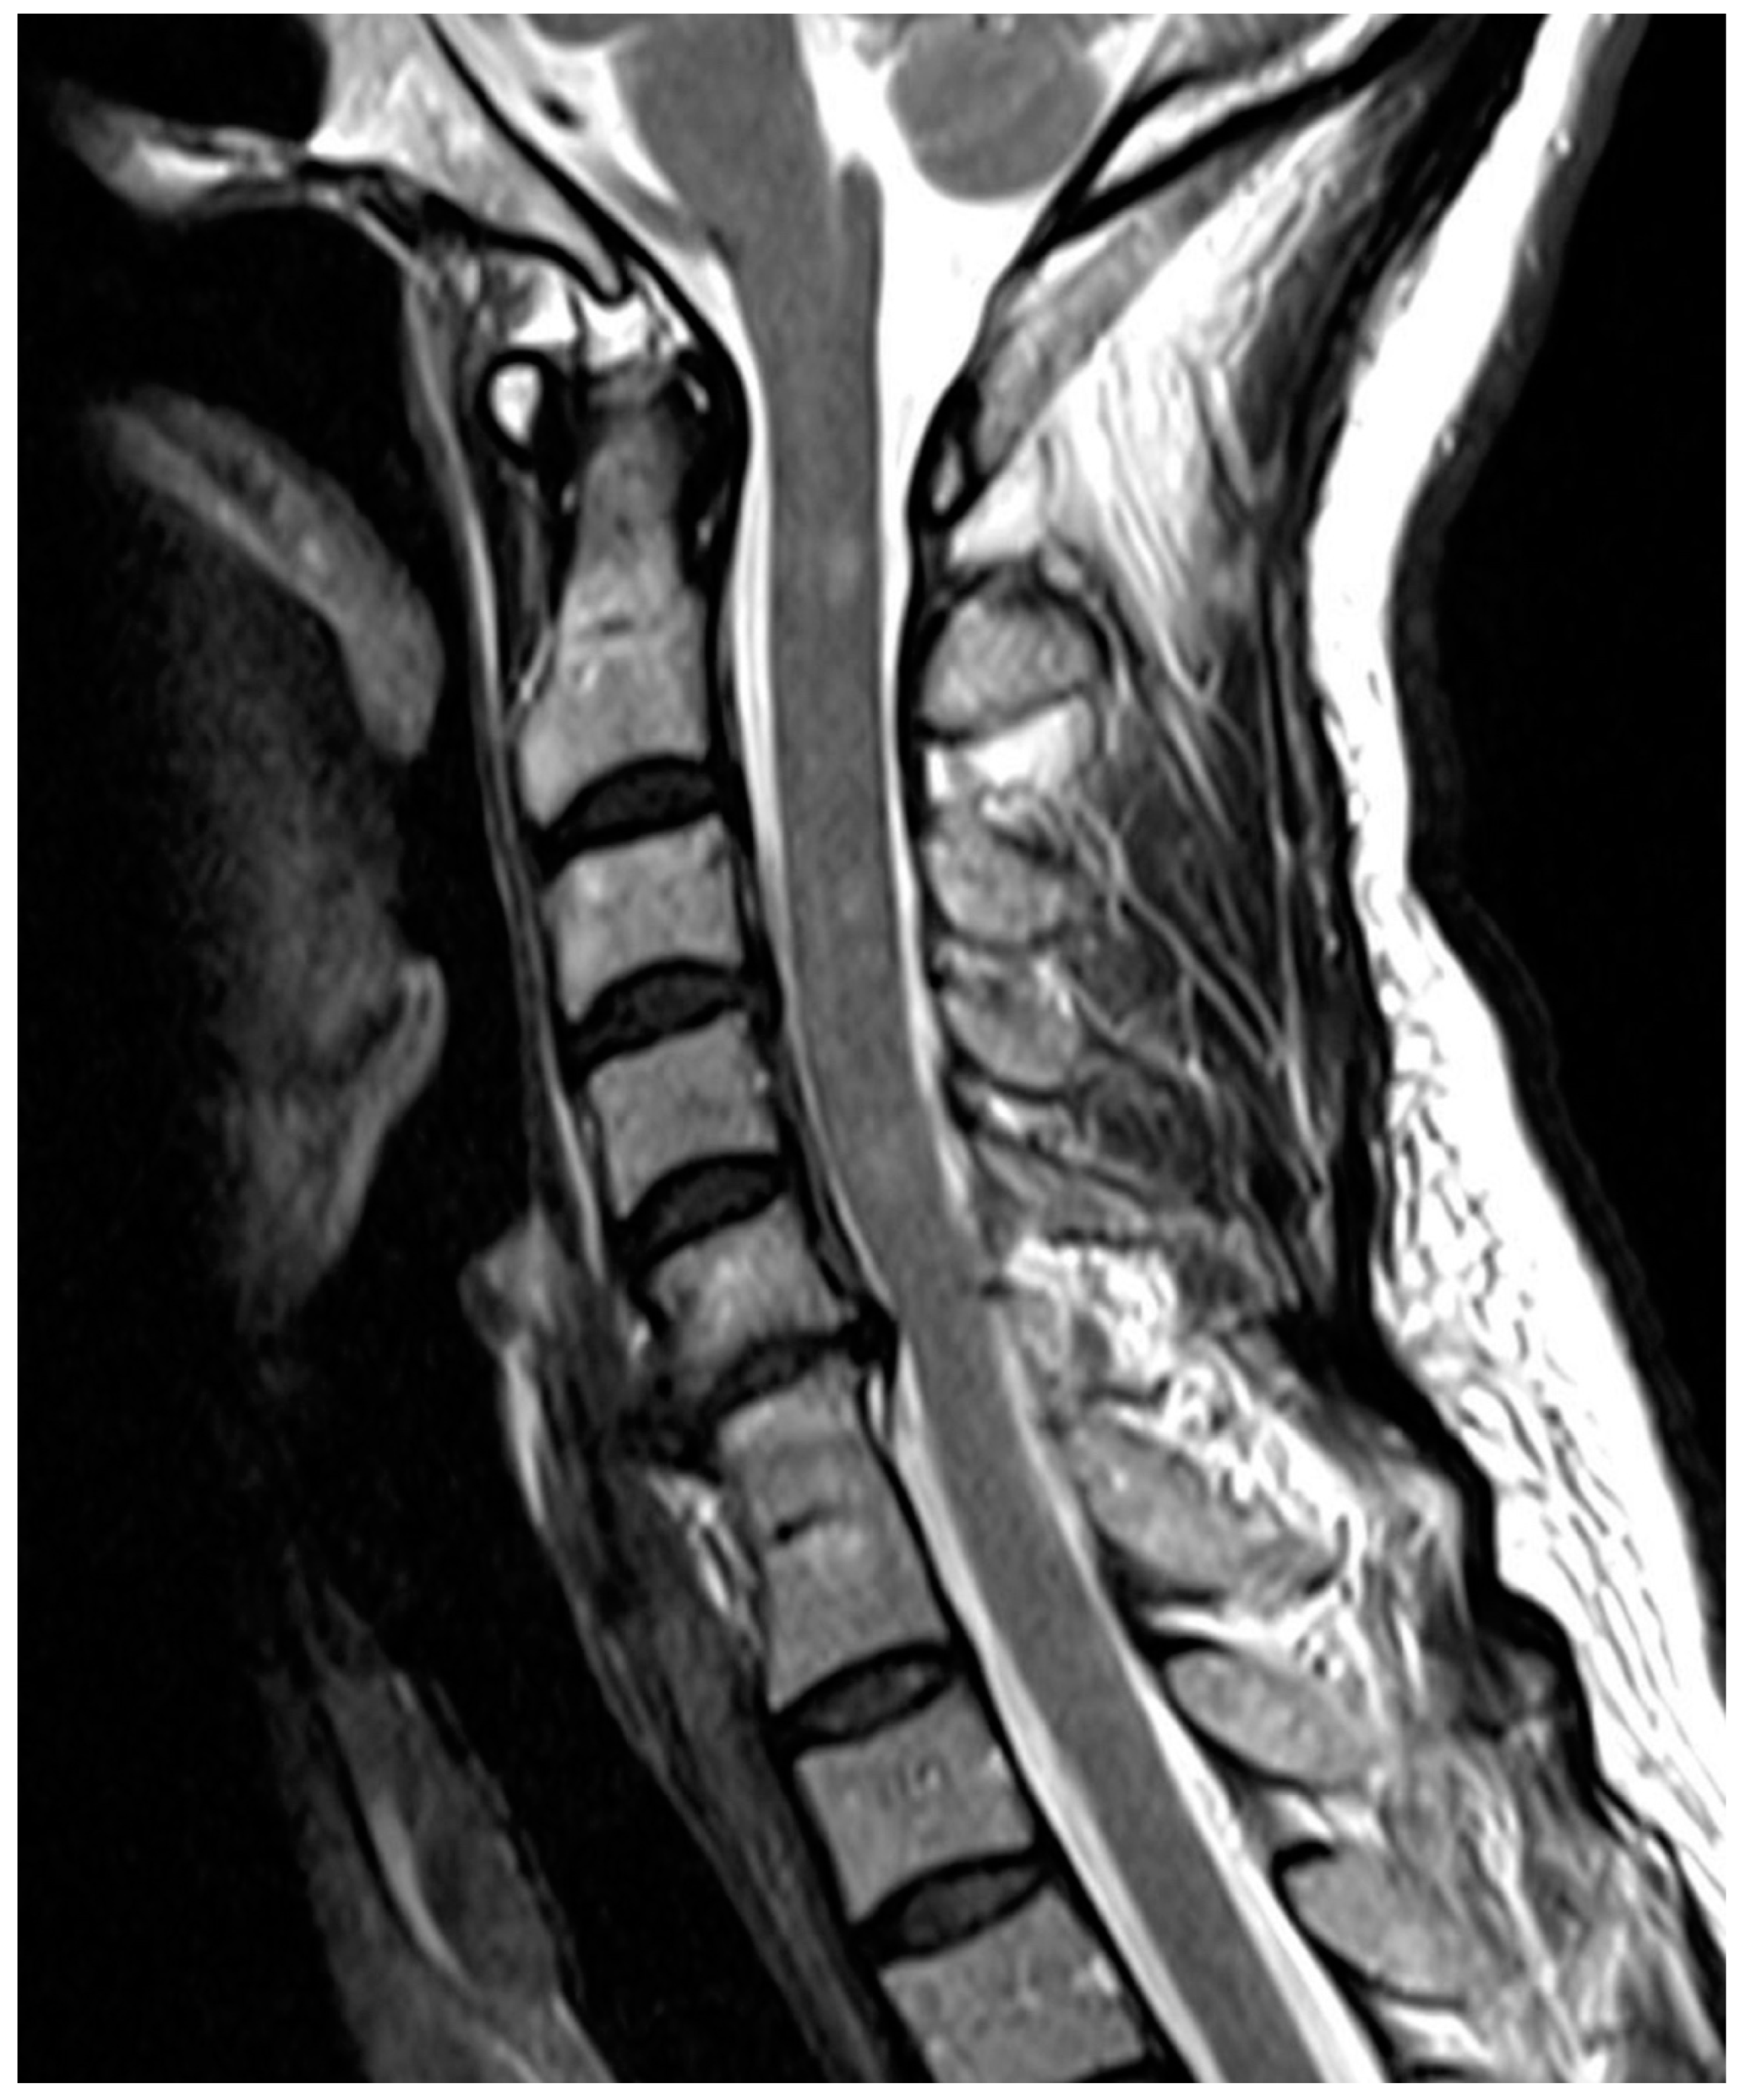

Are Congenital Cervical Block Vertebrae a Risk Factor for Adjacent Segment Disease? A Retrospective Cross-Sectional CT and MR Imaging Study